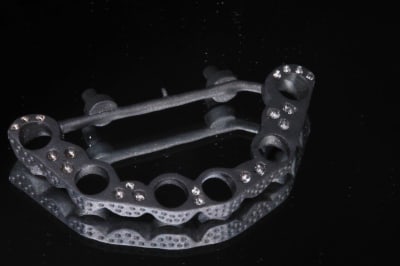

> c est un guide coulé ? en titane ?

Me revoici :)

c'est vrai que je ne suis plus tous les jours sur eugenol...

Le guide est en résine, mais j'en ai fait aussi en titane en frittage laser chez matérialise ( 120 euro, a peut près ). la tu as un cas ou l'étage clavette est en titane, et les accessoires imprimé resine ( tu peux retrouver la video du cas facilement, je pense ), l'armature du bridge prov en titane.

J'ai fait aussi guide tout métal, et guide metal servant également d'armature de bridge.

C'était en fait l’objet de ma conf a l'ADF : si tu as une idée, le numérique te permet de la mettre en œuvre.

C'est beaucoup de temps d'apprentissage, mais après, tu fait ce que tu veux.

Le grand mérite de Posit, c'est avec son compère de l'époque, d'avoir trouver un moyen fiable de faire de super guides alors l'impression 3D était balbutiante.

Alain, je pense que tu travaille toujours en cire perdue. Pas de raison de changer un protocole que tu maitrise, mais , comme le pensait Hokusai, tu irais plus vite, ou moins vite en modélisant le guide et imprimer en resine calcinable ?